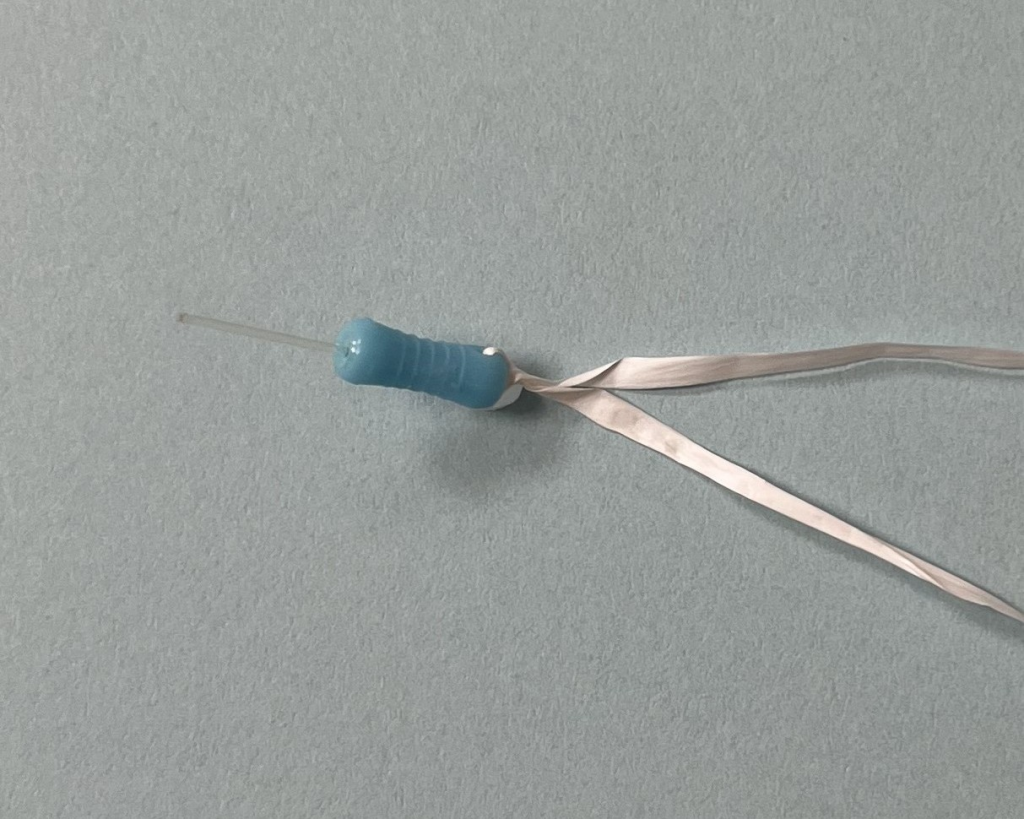

Add Floss to Pin

Be sure to attach floss to the handle of the pin to ensure it is not swallowed or aspirated during the procedure. See the picture above.